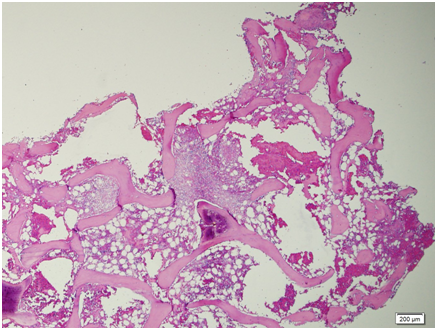

Figure 12 Scanning view: the bone marrow aspirate smear is cellular and polymorphous showing myeloid and mild increased in erythroid precursors in all stages of maturation with an M/S ratio of 1.2:1. No extraneous cells noted. Megakaryocytes are identified.

Figure 13 Low power view. The bone marrow core biopsy is hypercellular for age showing 80‒90% cellularity.